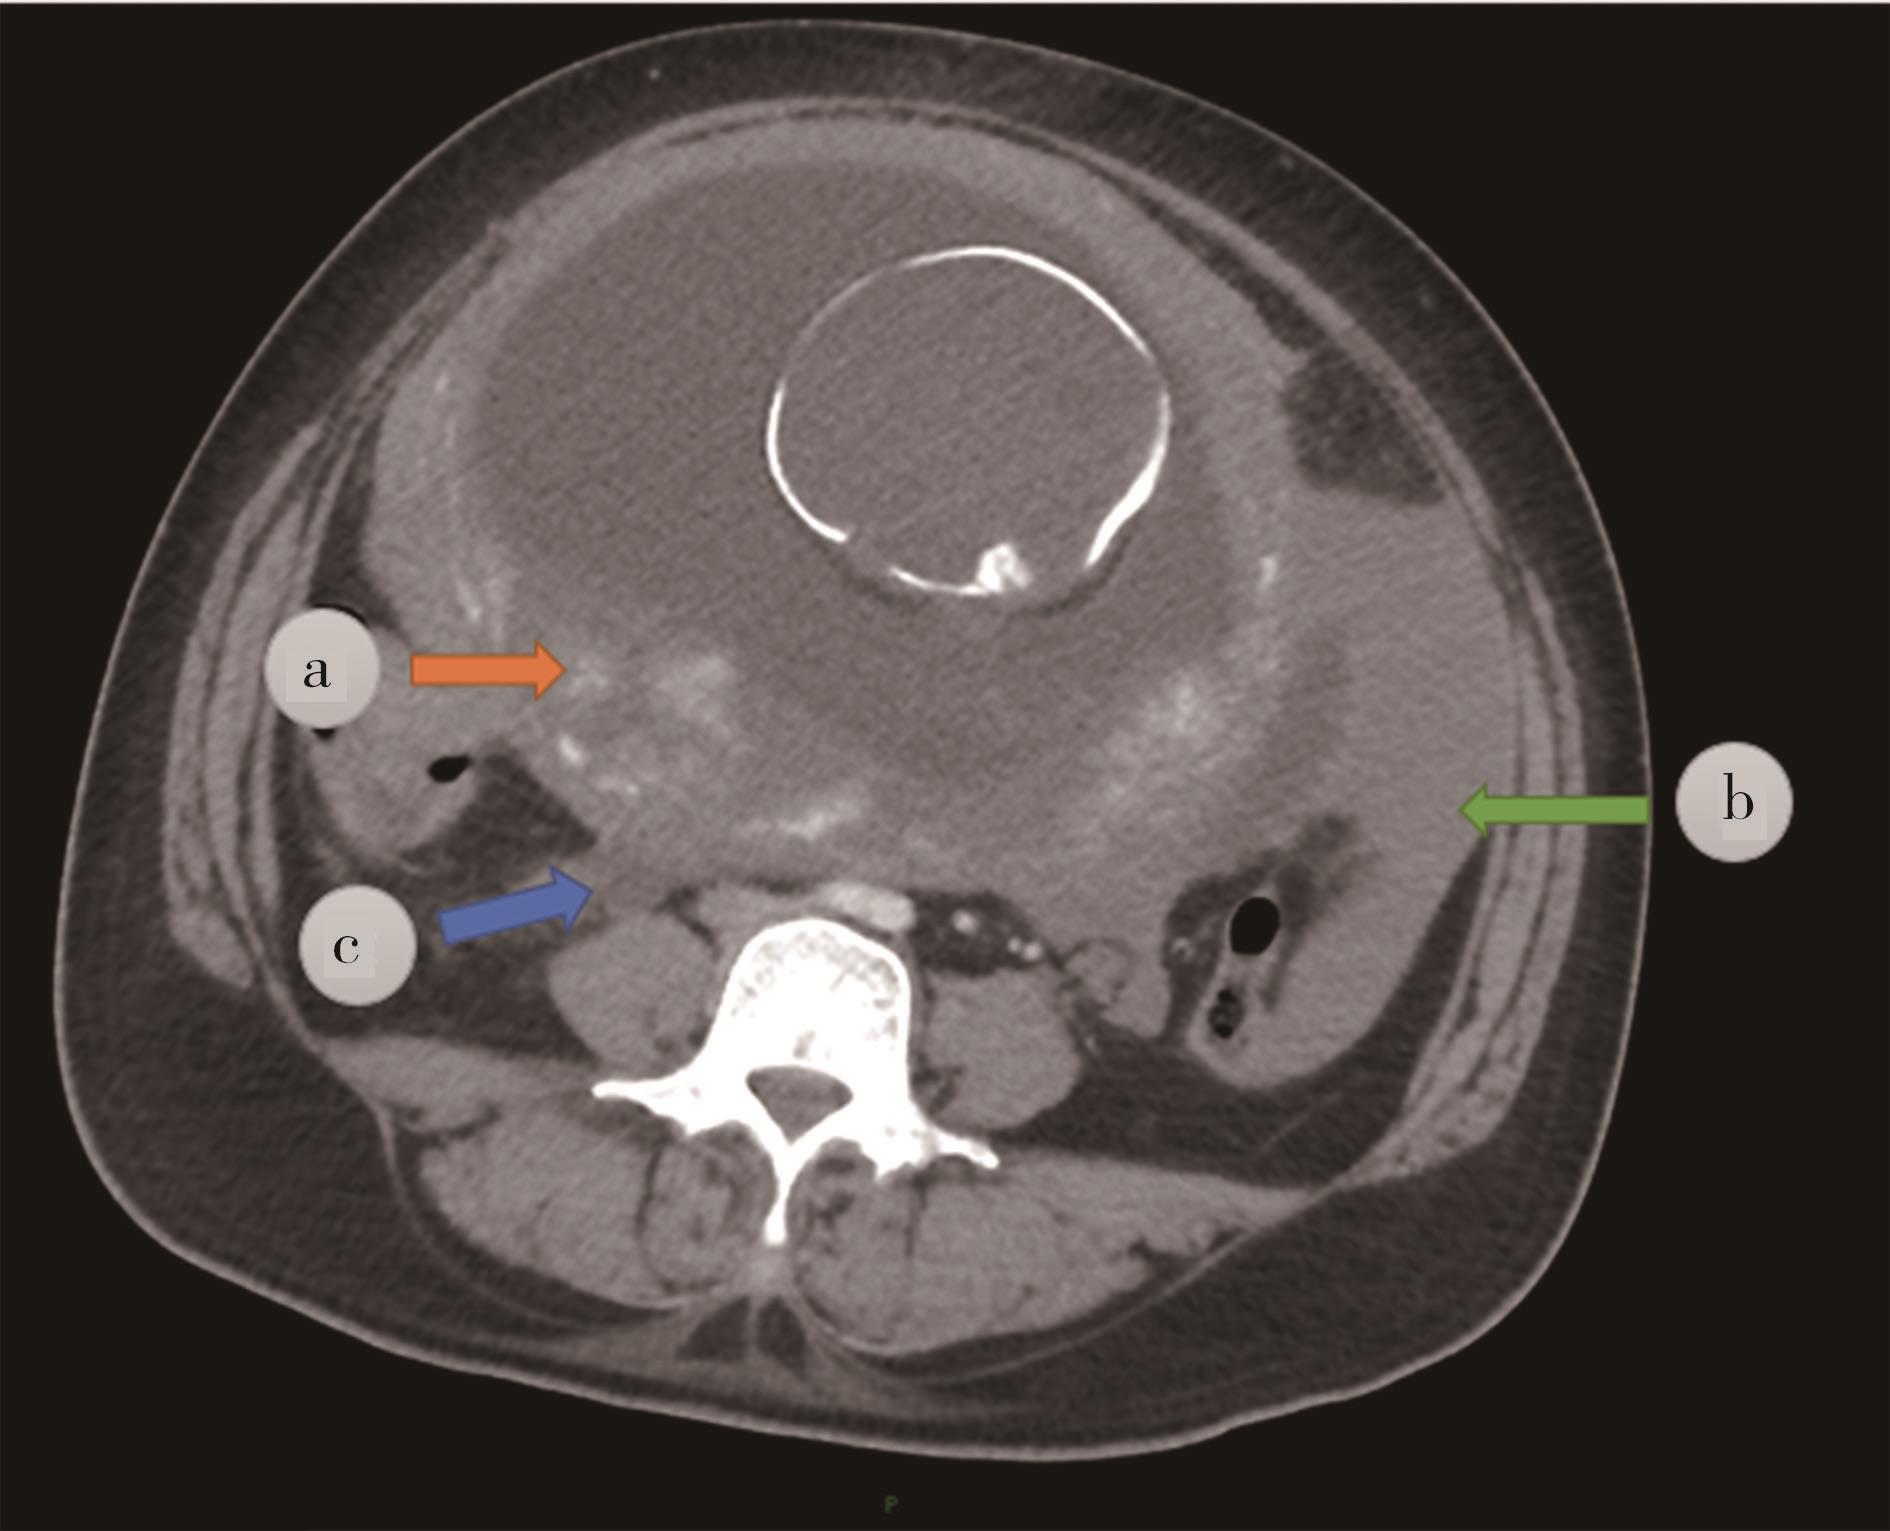

• “镜面人”保留左结肠动脉腹腔镜低位直肠癌根治术1例

2023, 48(7):853-856. DOI: 10.13406/j.cnki.cyxb.003278

摘要 (87) HTML (56) PDF 3.64 M (283) 评论 (0) 收藏